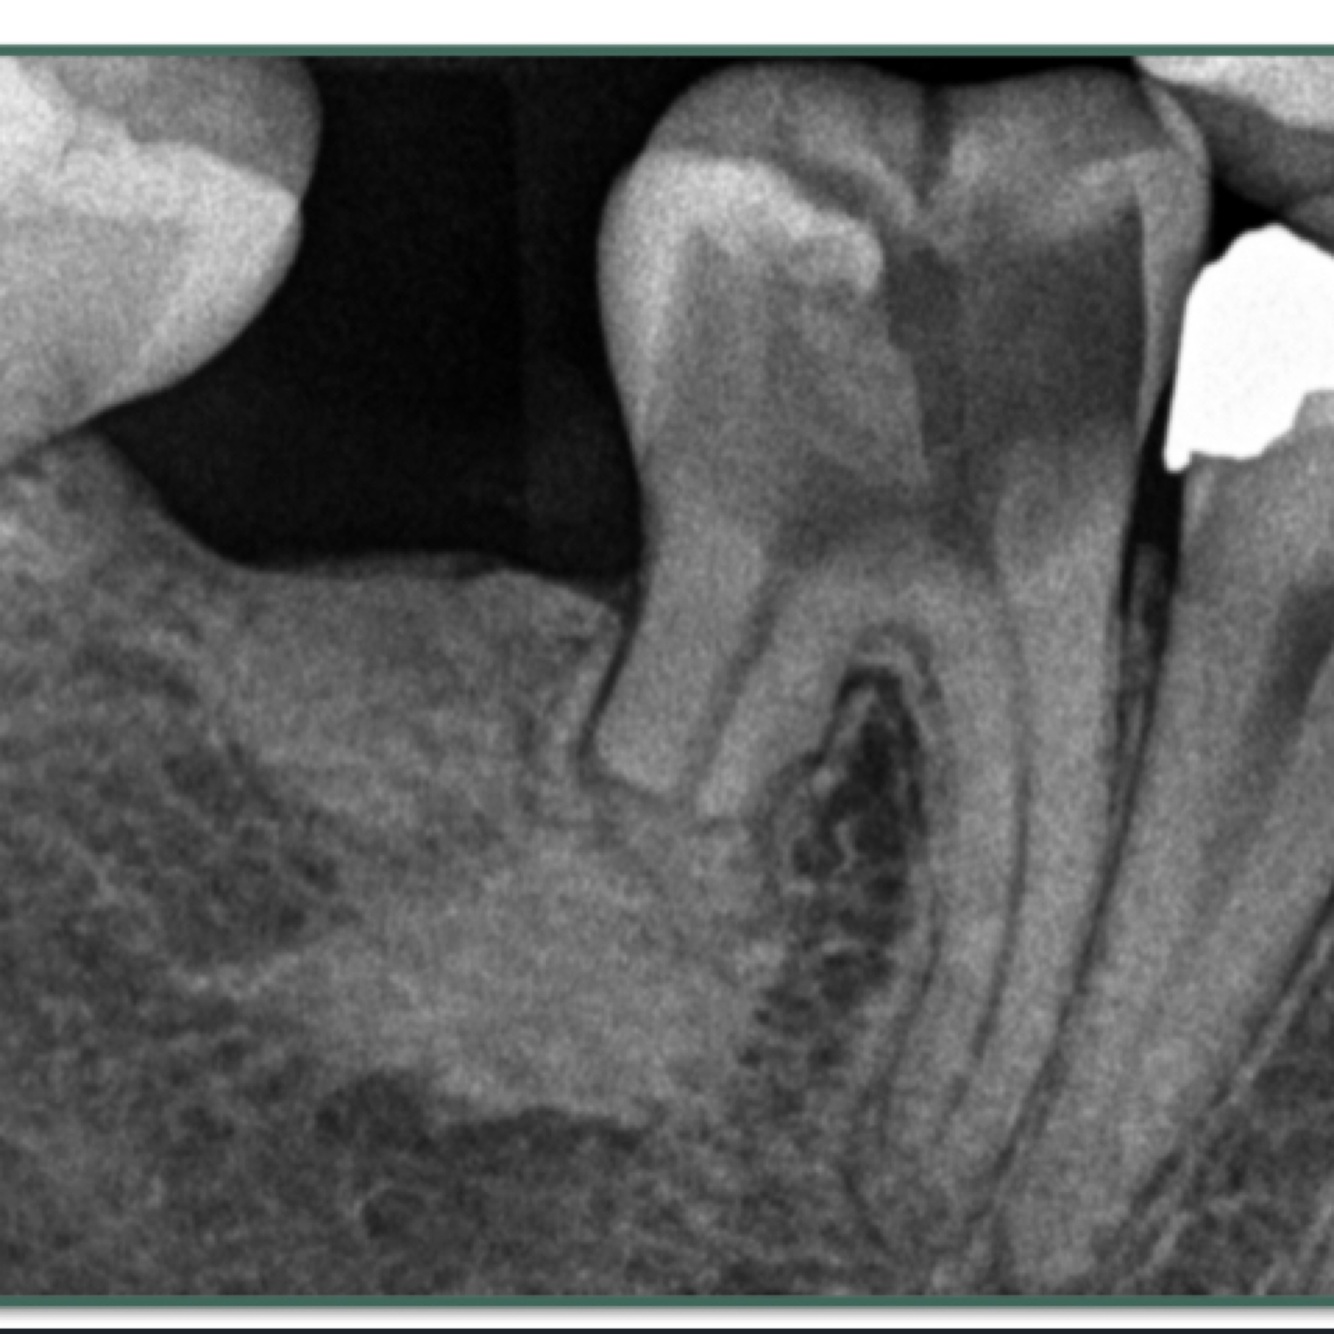

What is rareifying osteitis?

A

Localised loss of bone in response to inflammation

- always a secondary to primary pathology

• if near apex of tooth - look for pulpal / apical diagnoses